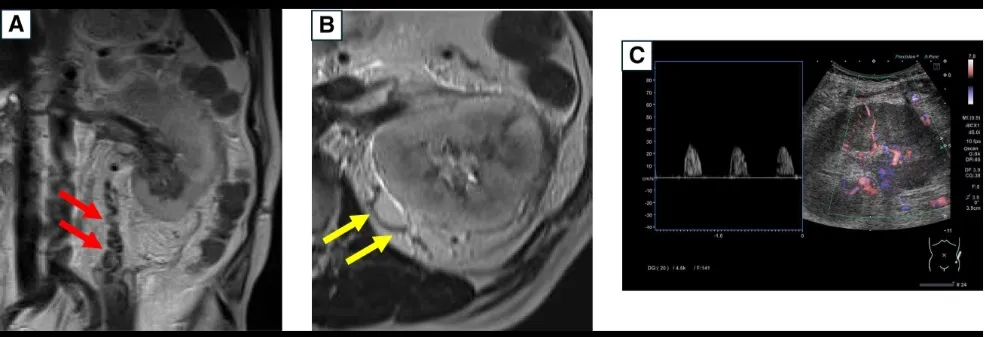

Hematúria e Lesão Renal Aguda em Paciente com Câncer Renal: Quando Pensar em Trombose da Veia Renal?